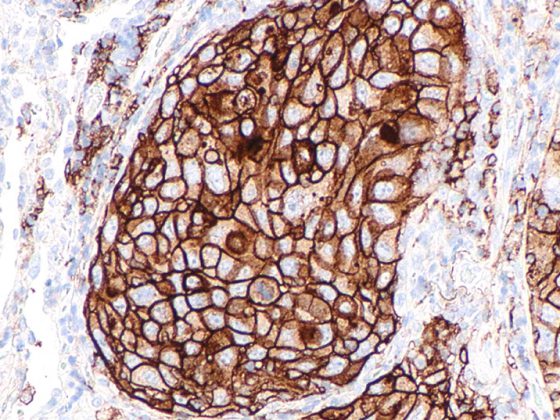

sneddwilk5_watermarkedwyjxyxrlcm1hcmtlzcjd

• Fallbericht

Subkorneale pustulöse Dermatose

• Allergologie und klinische Immunologie

• Cases

• Dermatologie und Venerologie

• Fortbildung

• Rx

Weiterlesen